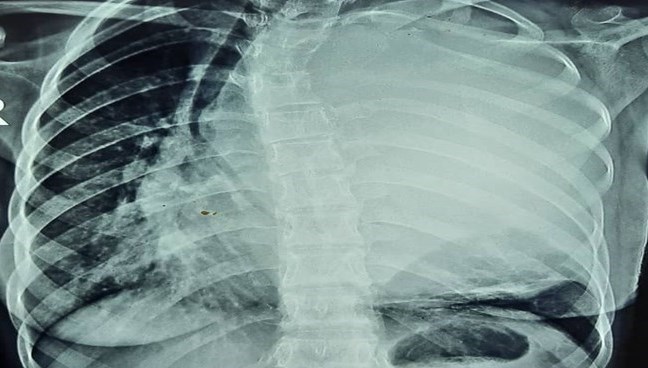

فوق تخصص جراحی قفسه سینه در زاهدان با بیان اینکه بیمار خانمی است که با شکایت تنگی نفس به بیمارستان مراجعه کرده بود بعد از انجام مراحل تشخیصی متوجه تودهای بزرگ در قفسه سینه بیمار شدیم، افزود: این توده به قدری بزرگ شده بود که روی قلب، آئورت و ریه بیمار به شدت فشار آورده بود تا حدی که بیمار قادر به تنفس معمولی هم نبود.

پزشک معالج با پیچیده خواندن روند انجام این عمل جراحی، گفت: بیمار بعد از طی مراحل سخت بیهوشی که توسط کادر مجرب بیهوشی انجام شد مورد عمل جراحی فوق تخصصی قفسه سینه قرار گرفت و توانستیم تودهای به بزرگی 2 کیلوگرم و به قطر 20 سانتیمتر را پس از جدا کردن از قلب، ریه و آئورت از قفسه سینه خارج کنیم.